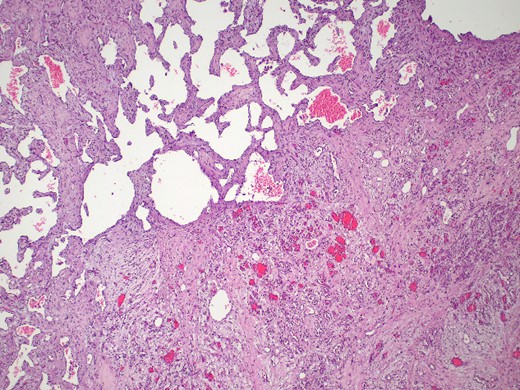

The pathology report confirmed the diagnosis of a mixed cavernous-capillary type cardiac hemangioma (Fig. 3). The gross pathological cut surfaces showed polypoid mass with a spongy light-to-dark brown appearance and focal fibrosis. The tumor involved tricuspid valve and resection margin (Fig. 2B). The histology showed the proliferation of capillary-sized blood vessels admixed with dilated thin-walled blood vessels. The vascular channels were lined by flat to plump endothelium. No nuclear pleomorphism, mitosis, or tumor necrosis was identified (Fig. 3).

Mixed cavernous-capillary hemangioma. The histologic examination reveals dilated thin-walled blood vessels (left upper) admixed with capillary-sized blood vessels (right lower) on fibrotic stroma (hematoxylin and eosin, 40x).